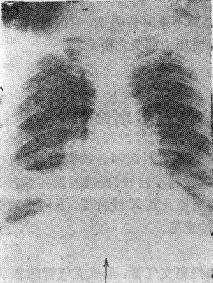

2.支气管腔外压性梗阻 如淋巴结肿大、血管环压等图115-1右下肺不张

图115-1 右下肺不张